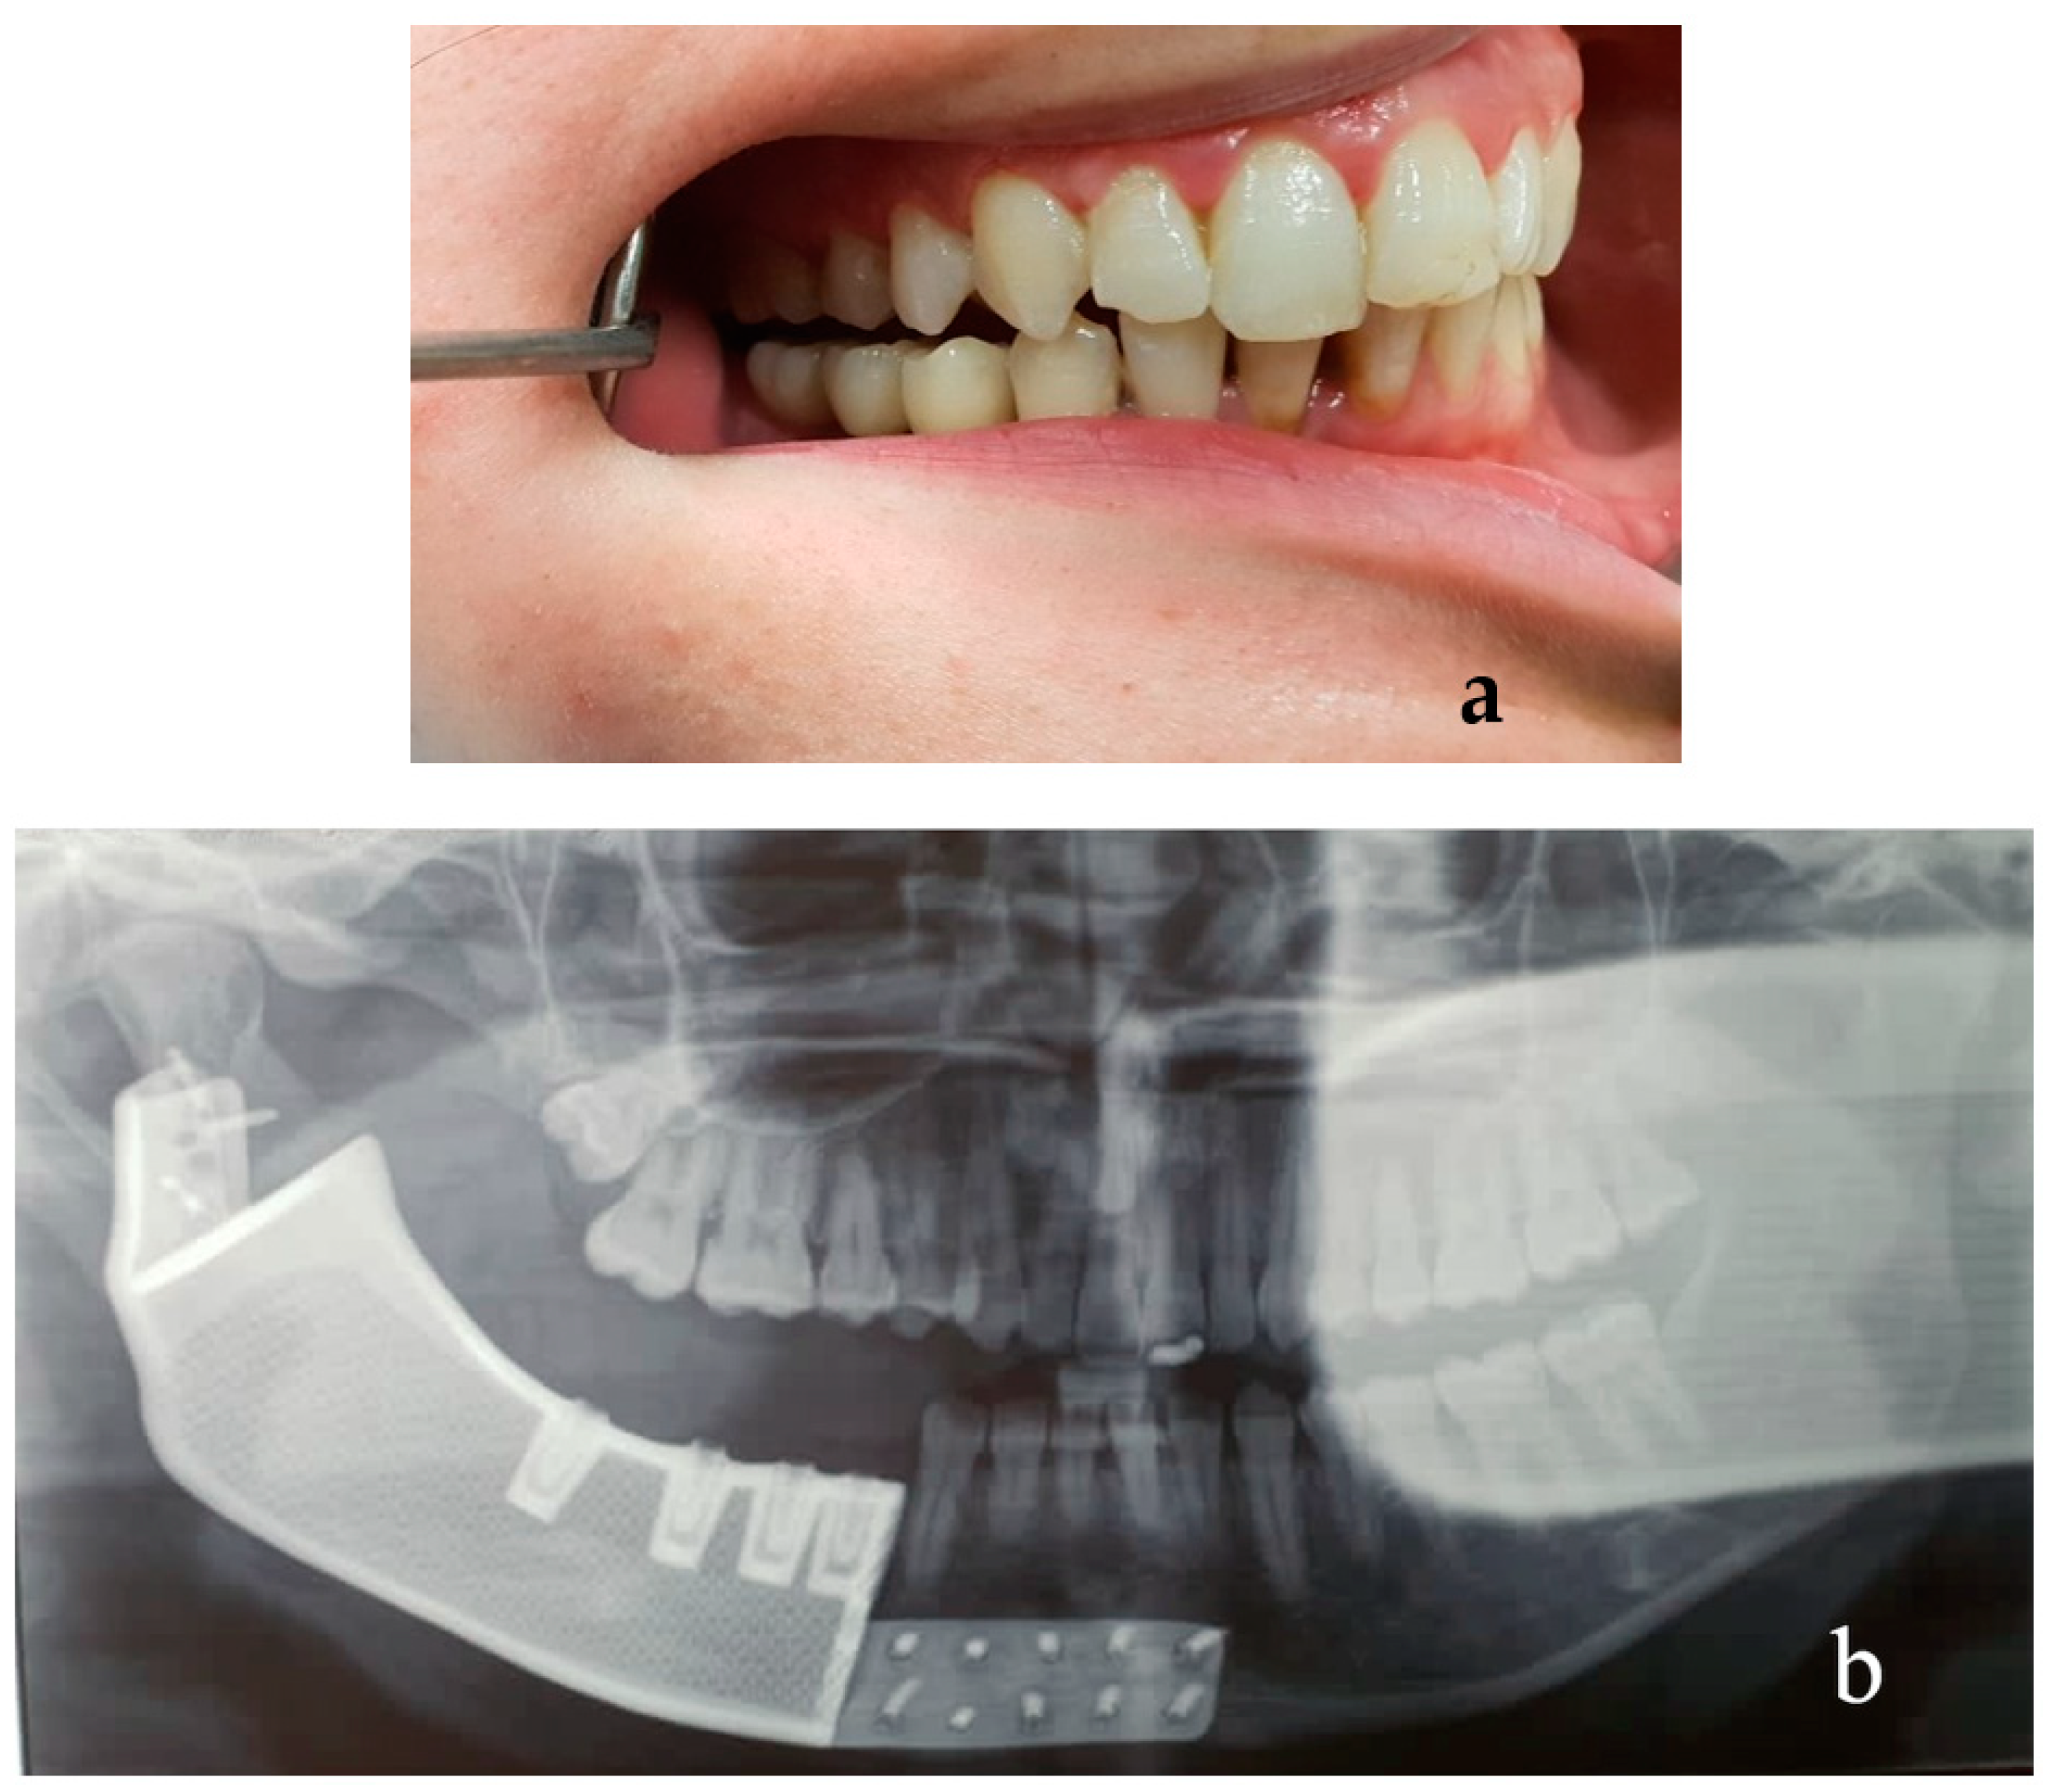

2.5. Results Case #1

2.9. Results Case #2